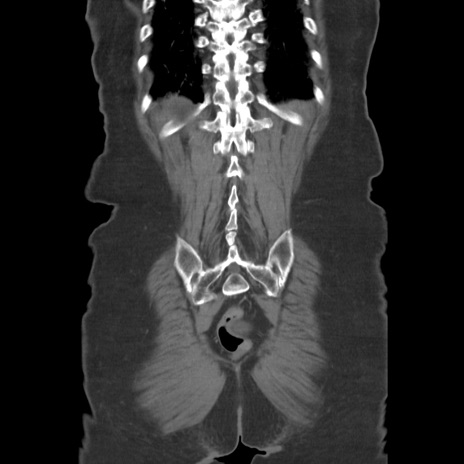

症例19(冠状断像)

【症例】80歳代女性

【主訴】下腹部痛

【現病歴】約8時間前より下腹部痛の出現あり、救急外来受診。

【既往歴】両側付属器切除

【身体所見】意識清明、下腹部正中に手術痕あり、その部位に一致して圧痛と反跳痛あり。腸蠕動音は亢進。

【データ】WBC 9300、CRP 0.15